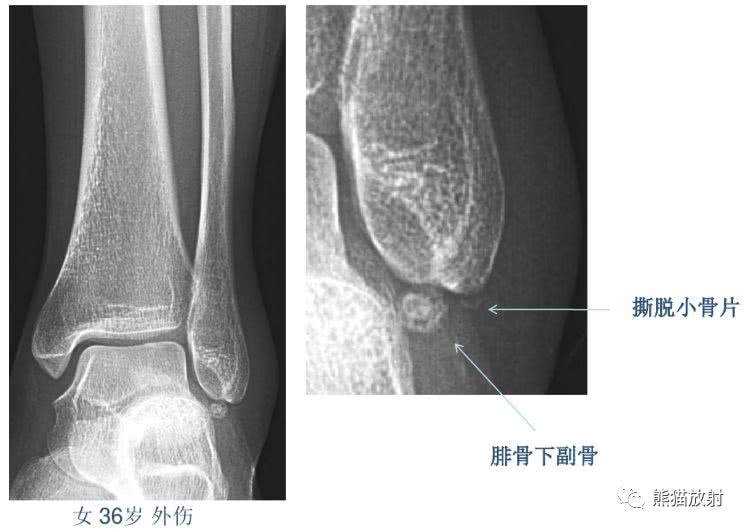

籽骨、副骨、永存骨骺、撕脱骨折?读完此文,你